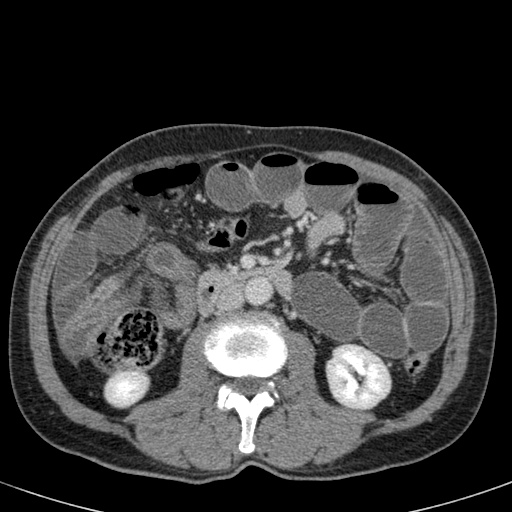

Tắc ruột dạng quai kín với các quai ruột giãn xếp theo hình nan hoa. Có dày thành ruột và phù nề mạc treo gợi ý thiếu máu cục bộ

Một hình ảnh quan trọng khác của tắc ruột dạng quai kín là các quai ruột non giãn xếp theo hình nan hoa với các mạch máu mạc treo hội tụ về một điểm trung tâm.

Hình ảnh này hầu như luôn do xoắn ruột non gây ra.

Các dấu hiệu thiếu máu cục bộ trong tắc ruột dạng quai kín tương tự như ở bệnh nhân thiếu máu mạc treo do các nguyên nhân khác:

- dày thành ruột

- phù nề mạc treo

- cổ trướng

- sự ngấm thuốc của thành ruột trong thiếu máu cục bộ có thể bình thường, tăng hoặc giảm.

Nếu quai kín dài hơn và định hướng vuông góc với mặt phẳng cắt, chúng ta sẽ thấy một cụm quai ruột như trong ca lâm sàng bên trái.

Đôi khi điều này khó nhận biết chỉ trên các lát cắt ngang và các tái tạo mặt phẳng coronal hoặc sagittal có thể hữu ích.

Trong ca này, cũng có phù nề mạc treo và cổ